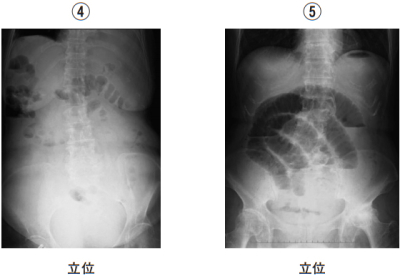

腹部エックス線写真を別に示す。腹部の診察で波動が認められると考えられるのはどれか。

腹部診察で波動を認めるのは腹水貯留時。

④は腹水貯留により腹部の透過性が低下している。